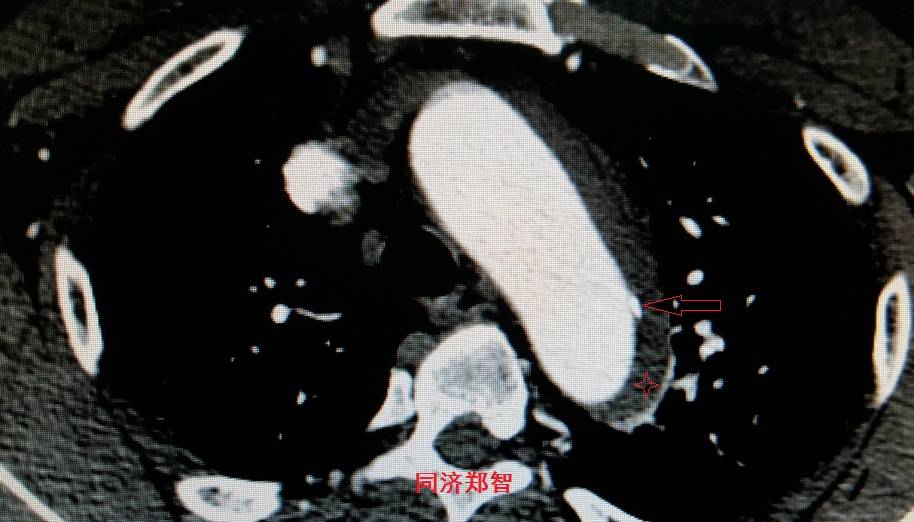

病例五

平扫CT提示主动脉弓层面及右肺动脉层面均可见主动脉血管腔内的内膜片影(红色箭头所示),CTA显示为A型主动脉夹层。